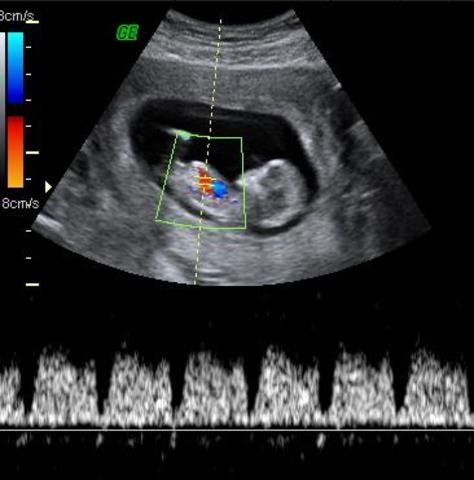

• Eco Doppler color

Eco Doppler color

"Ecografía en color que permite evaluar el flujo sanguíneo en cualquier arteria o vena. Es de especial relevancia para el estudio del cordón umbilical, la circulación cerebral y cardíaca fetal, así como la circulación uterina." (Inatal)